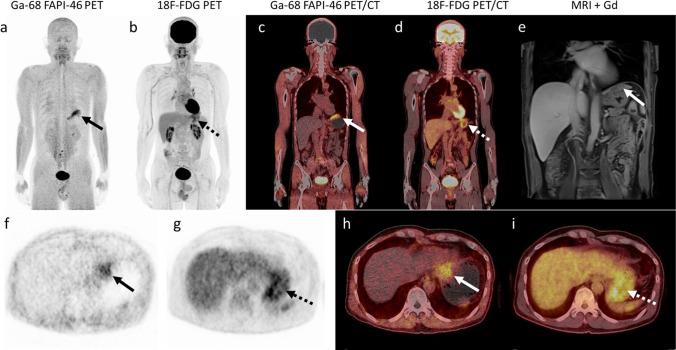

The 27 patients had a median age of 68 years (interquartile range: 60-74 years; 21 men). Primary intrahepatic tumours were reported in 13 patients (15 imaging studies) with cholangiocarcinoma (CCA) and in 14 patients with hepatocellular carcinoma (HCC). All intrahepatic lesions detectable on MRI were also detected on [ Ga]Ga-FAPI-46 PET/CT giving a sensitivity of 100% (19/19), whereas the sensitivity of [F]FDG PET/CT was 58% (11/19). All intrahepatic lesions were detected on [ Ga]Ga-FAPI-46 PET/CT, on which they showed higher activity (median SUVmax: 15.61 vs. 5.17; P < .001) and higher target-to-background ratio (TBR; median, 15.90 vs. 1.69, P < .001) than on [F]FDG, especially in patients with CCA (median TBR, 21.08 vs. 1.47, respectively; P < .001). The uptake positivity rate in regional node metastasis was 100% (12/12) on [ Ga]Ga-FAPI-46 PET/CT compared with 58% (7/12) on [F]FDG PET/CT. All patients with distant metastasis (100%, 14/14) were detected on both [F]FDG and [ Ga]Ga-FAPI-46 PET/CT imaging, although more distant metastatic lesions were detected on [ Ga]Ga-FAPI-46 PET/CT than on [F]FDG (96% (42/44) vs. 89% (39/44), respectively).

27 例患者的中位年龄为 68 岁(四分位距:60-74 岁;21 例男性)。13 例患者(15 项影像学研究)报告原发性肝内肿瘤为胆管细胞癌(CCA),14 例患者为肝细胞癌(HCC)。MRI 上可检测到的所有肝内病变在 [68Ga]Ga-FAPI-46 PET/CT 上也均有检出,其灵敏度为 100%(19/19),而 [F]FDG PET/CT 的灵敏度为 58%(19/19)。所有肝内病变在 [68Ga]Ga-FAPI-46 PET/CT 上均有检出,在该检查中它们显示出更高的活性(中位 SUVmax:15.61 比 5.17;P<0.001)和更高的靶-背景比(TBR;中位数,15.90 比 1.69,P<0.001),尤其是在 CCA 患者中(中位 TBR,分别为 21.08 比 1.47;P<0.001)。在区域淋巴结转移中,[68Ga]Ga-FAPI-46 PET/CT 的摄取阳性率为 100%(12/12),而 [F]FDG PET/CT 的摄取阳性率为 58%(7/12)。所有远处转移患者(100%,14/14)在 [F]FDG 和 [68Ga]Ga-FAPI-46 PET/CT 成像上均有检出,尽管 [68Ga]Ga-FAPI-46 PET/CT 比 [F]FDG 检测到更多的远处转移病灶(96%(42/44)比 89%(39/44))。